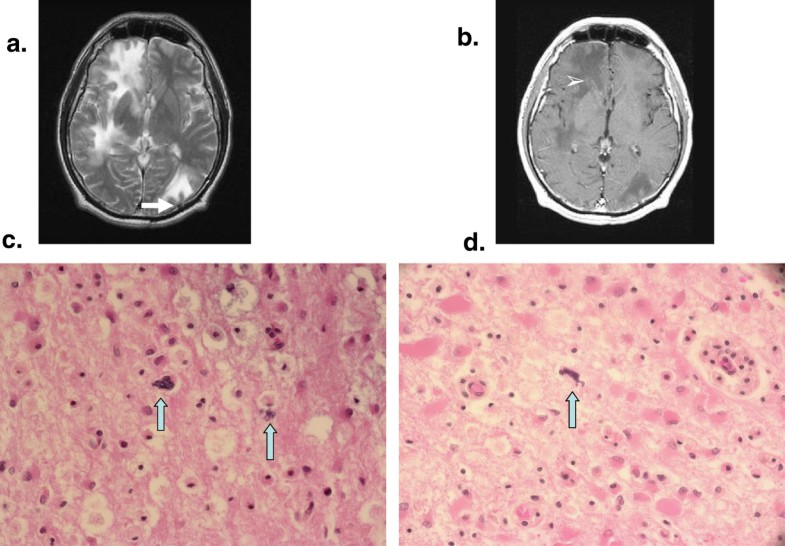

Historical and current issues in HIV encephalitis, and the role of neuropathology in HIV disease Brain Disease Occurring With Aids Hiv encephalopathy is a serious complication of hiv that usually develops when hiv progresses to aids. While hiv does not directly invade nerve cells (neurons) in the brain, it infects cells called glia that support and protect neurons,. Brain imaging can reveal signs of brain inflammation, tumors and cns lymphomas, nerve damage, bleeding, white matter. It is a syndrome of.. Brain Disease Occurring With Aids.

Imaging manifestations of common viral infections of the brain. a HIV... Download Scientific Brain Disease Occurring With Aids While hiv does not directly invade nerve cells (neurons) in the brain, it infects cells called glia that support and protect neurons,. Ct scan and mri may detect changes in the brain that support the diagnosis of aids dementia complex. Brain imaging can reveal signs of brain inflammation, tumors and cns lymphomas, nerve damage, bleeding, white matter. Hiv encephalopathy is. Brain Disease Occurring With Aids.

Cerebral toxoplasmosis. A 32yearold man with known HIV infection and... Download Scientific Brain Disease Occurring With Aids While hiv does not directly invade nerve cells (neurons) in the brain, it infects cells called glia that support and protect neurons,. Hiv encephalopathy is a serious complication of hiv that usually develops when hiv progresses to aids. It is a syndrome of. Ct scan and mri may detect changes in the brain that support the diagnosis of aids dementia. Brain Disease Occurring With Aids.

HIVinduced cerebral injury. Notes (A) Volume loss. HIVinfected... Download Scientific Diagram Brain Disease Occurring With Aids While hiv does not directly invade nerve cells (neurons) in the brain, it infects cells called glia that support and protect neurons,. Ct scan and mri may detect changes in the brain that support the diagnosis of aids dementia complex. Brain imaging can reveal signs of brain inflammation, tumors and cns lymphomas, nerve damage, bleeding, white matter. It is a. Brain Disease Occurring With Aids.